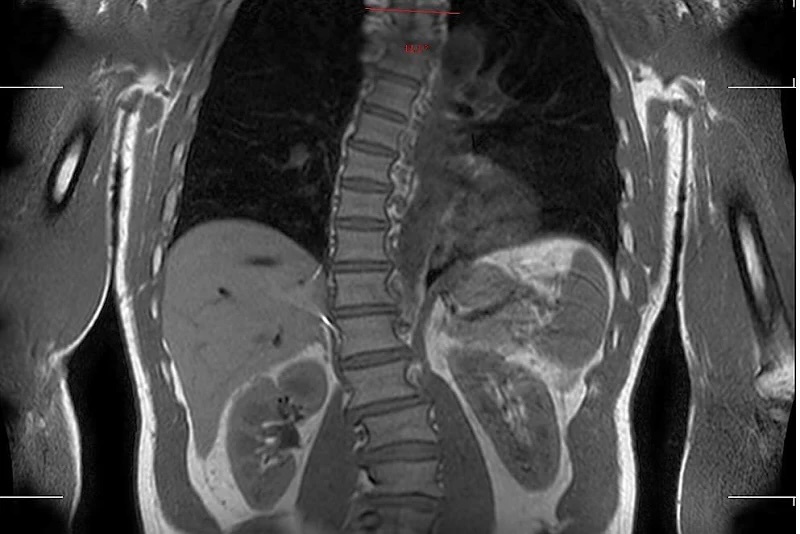

Aos 53 anos, Kelly Slater continua a ser uma das figuras mais influentes e inspiradoras do surf mundial. Com uma carreira que se estende por mais de três décadas — e que inclui 11 títulos mundiais — o norte-americano surpreendeu recentemente ao revelar, através das redes sociais, que sofre de uma escoliose severa, visível numa ressonância magnética que partilhou com os seus seguidores.

“Mostrar a minha coluna faz-me sentir exposto, mas acredito que é importante que as pessoas saibam que todos lidamos com dores físicas e que podemos encontrar formas de minimizar os efeitos ou até revertê-los.”

Slater realizou o exame numa clínica especializada em varrimentos corporais completos, a Prenuvo, num procedimento de alto custo (cerca de 2.500 dólares), que lhe foi oferecido gratuitamente. Os resultados revelaram alterações moderadas e alguns achados menores, que o campeão admite que irá monitorizar de perto.

Via Slater Instargram

Apesar da surpresa causada pela imagem da sua coluna, a revelação de Slater reforça o lado humano e vulnerável do atleta que, apesar de ter sido praticamente imbatível durante anos, não ficou imune às consequências físicas de décadas de surf de alto nível.